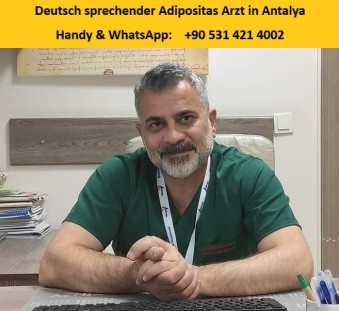

Op. Dr. Kutbettin Altun im Mediterranean Healing Hospital

deutsch sprechender Adipositasarzt

Allgemeinchirurg, Bariatrische Chirurgie, Adipositaschirurgie

Sprachen: deutsch, englisch, türkisch